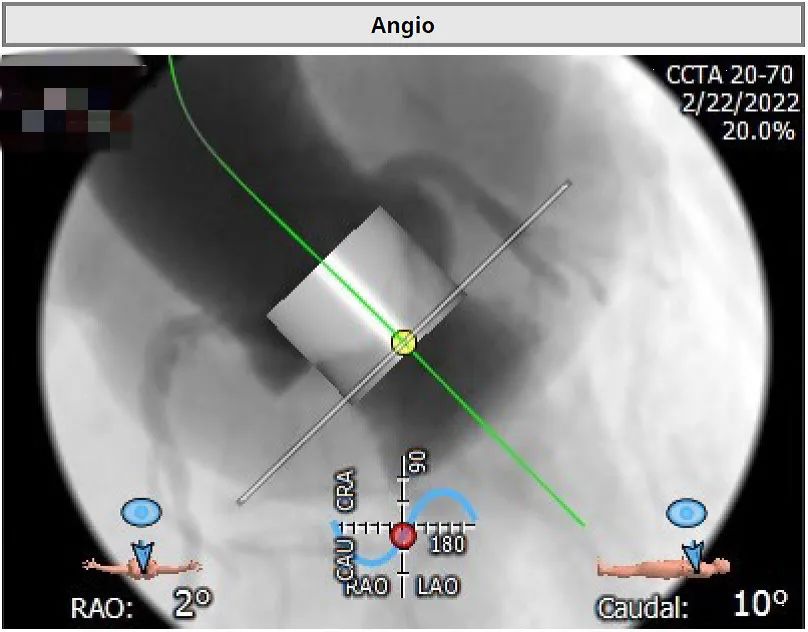

术中影像:

1.确认共平面